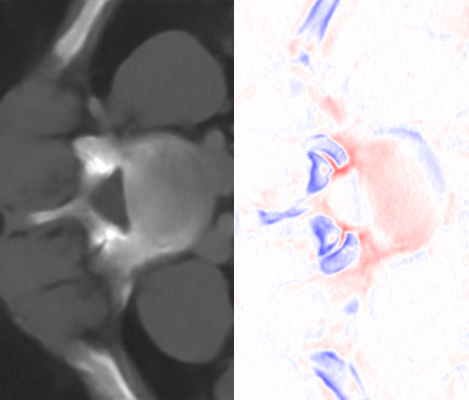

Refer to caption

HR

\stackanchorHRPSNR/SSIM

\stackanchor2D MDSR x424.01/0.7735

\stackanchor2D RDN x424.42/0.8101

\stackanchorMeta-SR x424.51/0.7995

\stackanchorAMI x425.84/0.8414

\stackanchor2D MDSR x619.75/0.4727

\stackanchor2D RDN x619.22/0.4482

\stackanchorMeta-SR x622.81/0.7069

\stackanchorAMI x623.42/0.7376

Figure 6: Visual comparisons of different methods against AMI. The difference maps are provided to the right of the results for better visualization. Images are best viewed when magnified.

Table 4 summarizes the performance of different implementations against AMI, evaluated on Isag(x,y,z)subscript𝐼𝑠𝑎𝑔𝑥𝑦𝑧I_{sag}(x,y,z), which we find to have better quantitative results than Icor(x,y,z)subscript𝐼𝑐𝑜𝑟𝑥𝑦𝑧I_{cor}(x,y,z) for all methods. For both rz=4subscript𝑟𝑧4r_{z}=4 and rz=6subscript𝑟𝑧6r_{z}=6, we found improvement in image quality from AMI over other methods, while Meta-SR and RDN have comparable performance. Despite the higher parameter number, MDSR ranked last due to using different substructures for different upsampling factors. For visual demonstration, we can see in Fig. 6 that AMI is able to recover the separation between the bones of the spine, while other methods lead to erroneous recovery where the bones are merged together. Compared to Meta-SR, AMI generates HW𝐻𝑊HW times less filter weights in its filter generation stage. With finite memory, this allows for GPUs to handle more slices in parallel, and achieve faster inference time per volume.